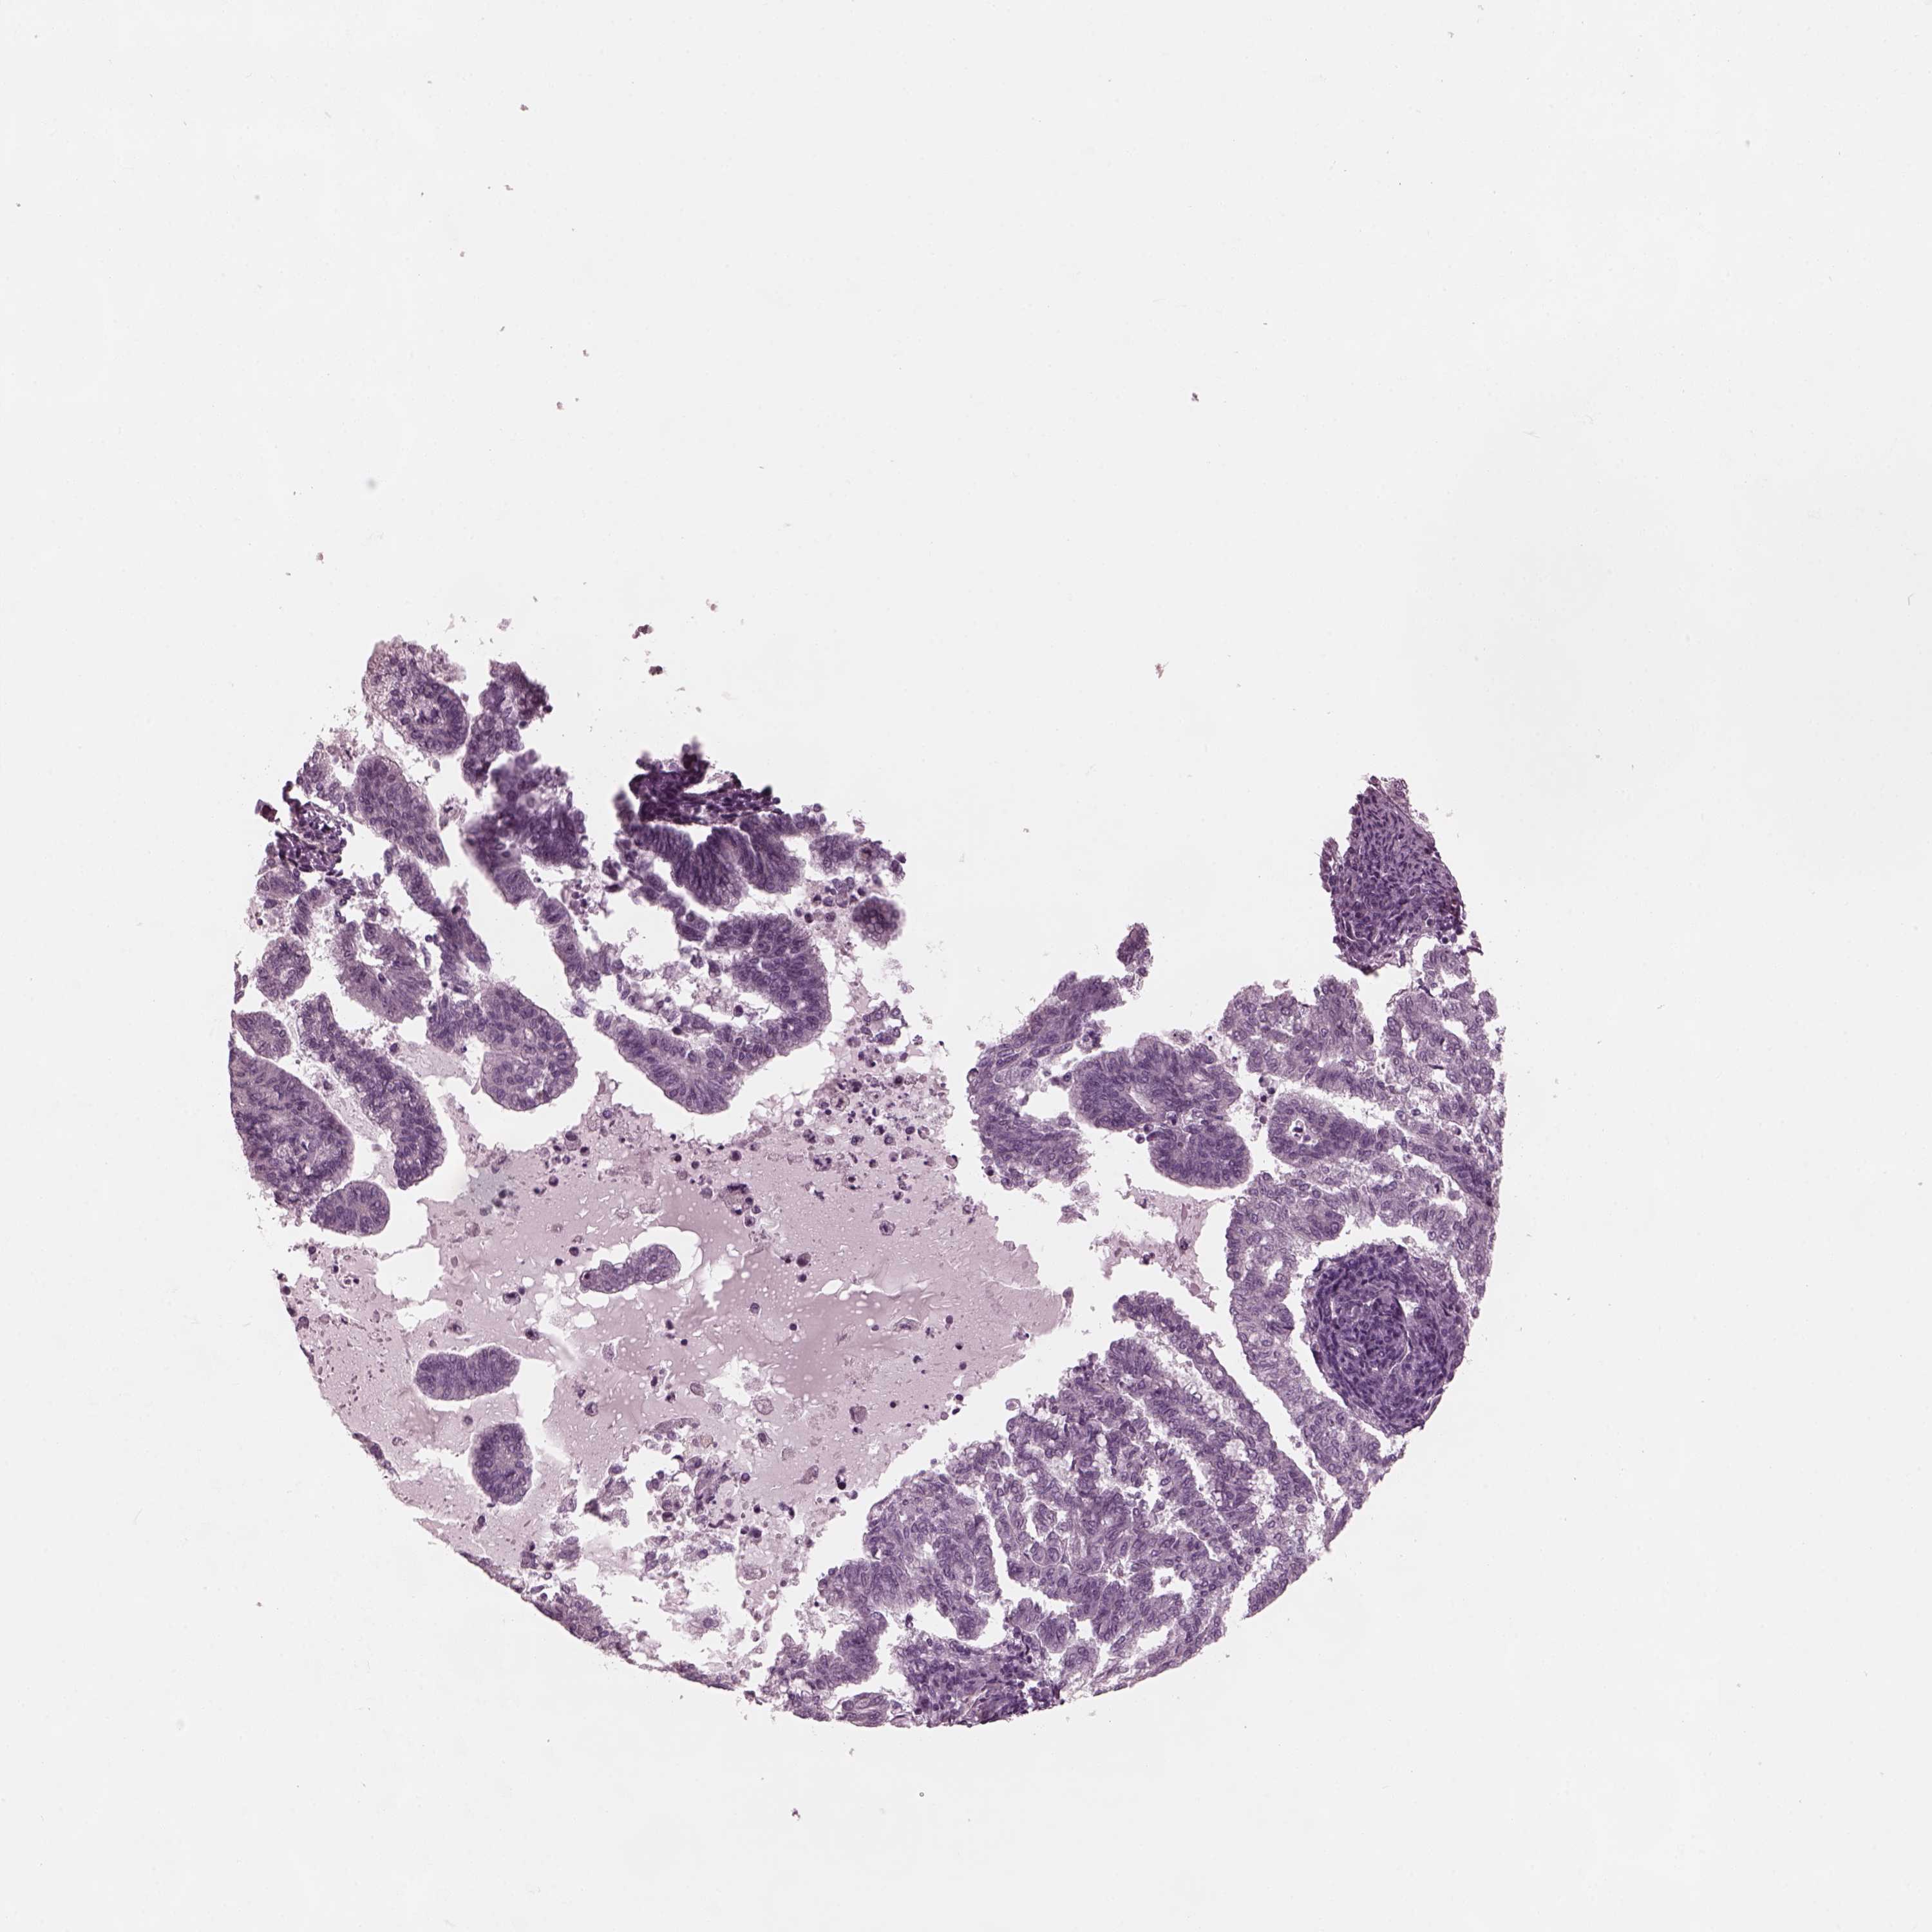

ENDOMETRIAL CANCER - Protein expressioni

A mouse-over function shows sample information and annotation data. Click on an image to view it in a full screen mode. Samples can be filtered based on level of antibody staining by selecting one or several of the following categories: high, medium, low and not detected. The assay and annotation is described here.

Note that samples used for immunohistochemistry by the Human Protein Atlas do not correspond to samples in the TCGA dataset.

Antibody stainingi

Antibody staining in the annotated cell types in the current human tissue is reported as not detected, low, medium, or high, based on conventional immunohistochemistry profiling in selected tissues. This score is based on the combination of the staining intensity and fraction of stained cells.

Each image is clickable and will lead to virtual microscopy that enables deeper exploration of all samples and also displays staining intensity scores, fraction scores and subcellular localization as well as patient and tissue information for each sample.

Antibody HPA038811

Staining

High

Medium

Low

Not detected

Intensity

Strong

Moderate

Weak

Negative

Quantity

>75%

75%-25%

<25%

None

Location

Nuclear

Cytoplasmic/membranous

Cytoplasmic/membranous,nuclear

Adenocarcinoma, NOS

Adenocarcinoma, metastatic, NOS